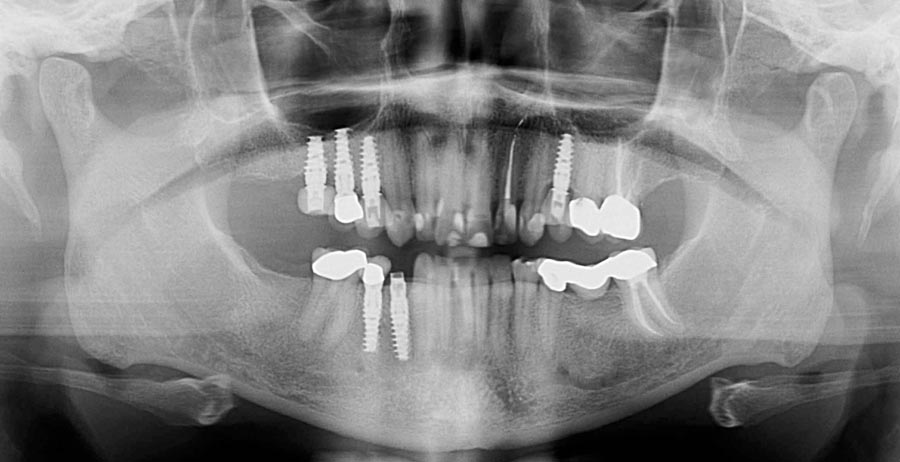

Smile GalleryImplant RestorationsFull Mouth Implant Restoration Full arch zirconia implant bridge (full smile) 1 of 37 Pre-op full smile Pre-op lips retracted Pre-op panoramic x-ray Extraction of strategic teeth Placement of implants Extraction of some remaining teeth after verification of adequate implant stability Occlusal view Post-op panoramic x-ray Immediately fabricated provisional restoration (tissue side view) Immediately fabricated provisional restoration (occlusal side view) Immediate provisional delivered on day of surgery Immediate provisional 2 weeks later Scalloped tissue developed from the provisional at 2 weeks Jig used for making a master impression Provisional in place (full smile) Provisional in place (lips retracted) Provisional in place (right side) Provisional in place (left side) Wax try-in (full smile) Wax try-in (right side full smile) Wax try-in (left side full smile) Wax try-in (full face, lips together) Wax try-in (full smile) Wax try-in (right side) Wax try-in (left side) Wax try-in (lips retracted) Full arch zirconia implant bridge on master cast (frontal view) Full arch zirconia implant bridge on master cast (occlusal view) Implant positions and soft tissue representation on master cast (occlusal view) Soft tissue representation on master cast (frontal view) Full arch zirconia implant bridge (tissue side view) Soft tissues on day of delivery (occlusal view) Soft tissues on day of delivery (frontal view) Full arch zirconia implant bridge delivered (lips retracted) Full arch zirconia implant bridge (lips retracted, close up) Post treatment panoramic x-ray Full arch zirconia implant bridge (full smile)